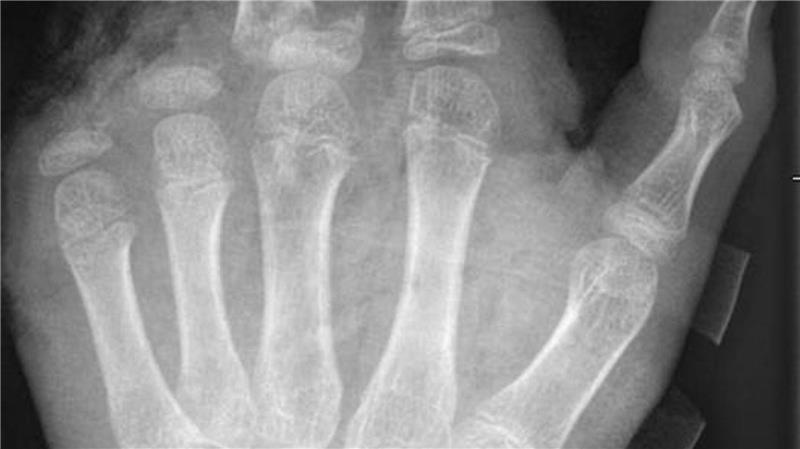

So kann ein Röntgenbild nach einer missglückten Böllerexplosion aussehen: Zwei Finger fehlen. Foto: -/UKB/dpa

„Der überwiegende Teil der Verletzungen trägt tatsächlich lebenslange Folgen mit sich, weil die Sprengkraft dazu führt, dass eben nicht nur einzelne Strukturen verletzt sind, sondern immer mehrere. Und das heilt praktisch nie ganz folgenlos ab.“ Zum Teil könnten Hände nicht mehr gerettet und müssten amputiert werden.